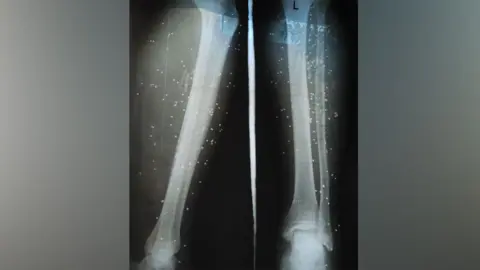

Half of the healthcare professionals stated that delays in treatment often led to severe complications in patients, including amputations and chronic mobility issues.